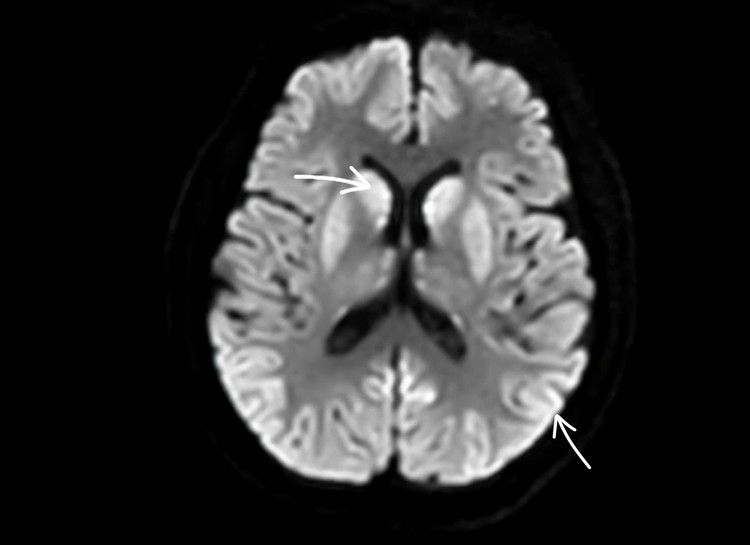

![]() |

| Não bệnh nhân bị tổn thương nặng, rất khó có thể hồi phục. Ảnh: BVCC. |